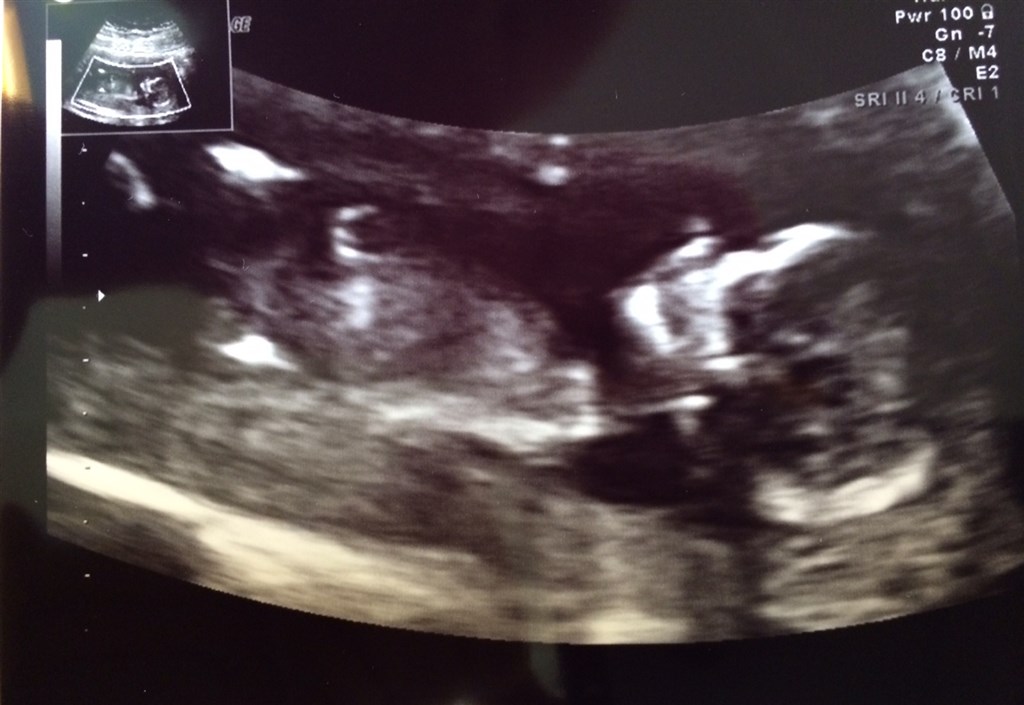

Hun startede med at vise os det bankende hjerte

Vi så at der var væske mavesækken, så den kan finde ud af at drikke, at der var væske i blæren, så den del også fungerer. To arme med en hånd på hver, og to ben med en fod på hver. Hjernen var som dem skulle være, og hun viste os et tydeligt næseben.

Rejen var ikk helt samarbejdsvillig da hun skulle måle nakkefolden, og hun brugte lang tid for at få et ordentligt billede. Det lykkedes til sidst og hendes udregninger gav os tallet 3200

Vedhæftede fotos (klik for at se i fuld størrelse)